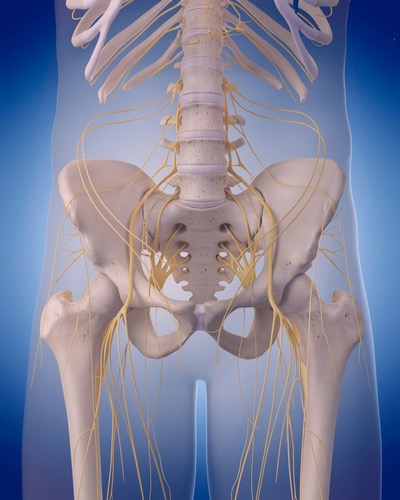

仙結節靭帯は坐骨結節を介してハムストリングスとつながりがあります。ハムストリングスが硬くなると、骨盤の動きが制限されます。そしてハムストリングスを緩めたとしてもこの仙結節靭帯が仙腸関節の動きを数㎜制限させるだけで腰痛や殿部の痛みが取りきれないのです。特に寝返りや立ち上がりなどの動き出しの腰痛はこの仙結節靭帯の影響が非常に大きいです。この仙結節靭帯を調整するだけであなたの腰痛治療の成果が5倍になります。

- 腰痛の原因が全て把握できるようになり、この仙結節靭帯の調整で痛みの改善は当然、戻りに対しても簡単に調整できるようになります。

陰部神経は仙骨神経叢から起こり、梨状筋と尾骨筋の間を通り、大坐骨孔から骨盤外へ出ます。ここで、下直腸神経が分かれ、そのすぐ後に会陰神経と陰茎背神経・陰核背神経の終枝に坐骨棘を周り、小坐骨孔から再び骨盤内へ入ります。

足のしびれ原因NO1の痛み痺れをとる坐骨神経リリーステクニック

坐骨神経痛は殿部~下肢後面に走る痛みとシビレを症状です。ヘルニアや腰部脊柱管狭窄症の疾患でよる表れる症状です。ヘルニアや腰部脊柱管狭窄症の疾患がなくても、例えば梨状筋がこの坐骨神経に刺激を与え神経症状が生じているケースもあります。刺激とは圧迫や滑走性低下による摩擦などを表していますが、坐骨神経とその周囲組織のリリースをすることで今まで取りきれなかった神経痛を解消させることができます。